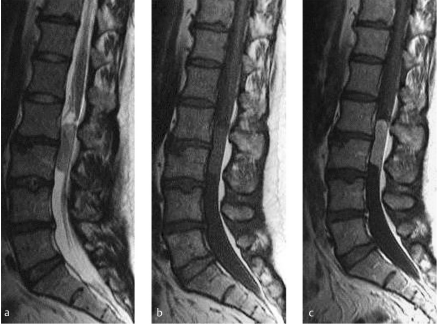

Describe the imaging findings in this patient with progressive lower limb weakness

The MRI reveals a mass lesion below the conus medullaris that may be associated with either the filum terminale or a cauda equina nerve root. The lesion enhances homogeneously with contrast administration and the differential diagnosis includes a myxopapillary ependymoma, peripheral nerve sheath tumour such as a schwannoma or neurofibroma and meningioma.